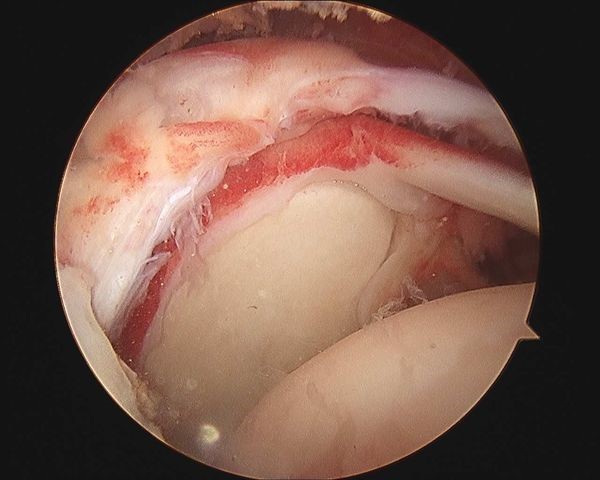

3.关节镜下肩袖修复

近年来,随着关节镜技术的提高和关节镜器械的发展,特别是锚钉(Anchor)技术的出现,大部分肩袖撕裂的修复已经能在全镜下完成了。全镜下肩袖修复包括单排缝合、双排缝合、桥式缝合等不同的方式。

全镜下技术与小切口修复技术哪种方法更好呢?科学研究结果告诉我们,两者效果相当,只是全镜下技术具有切口更小、三角肌损伤轻微、术后关节僵硬发生率低、恢复快等优点。

肩关节镜微创手术示意图 图片来源于网络,侵删

肩袖修补手术示意图 图片来源于网络,侵删